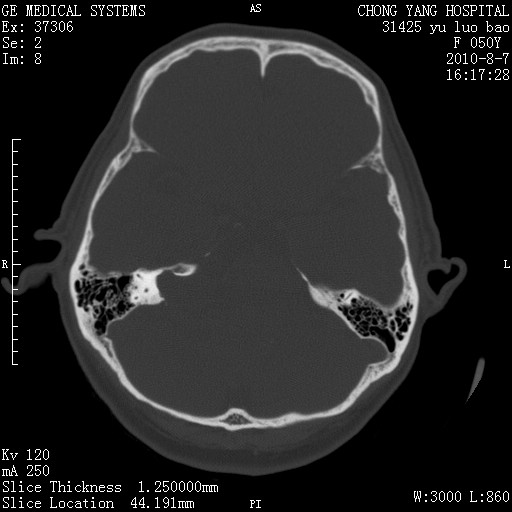

标题: CT28285:听力下降一年,头昏。 [打印本页]

标题: CT28285:听力下降一年,头昏。

右侧桥小脑角去等密度占位,右侧内听道扩大、骨质吸收,考虑:右侧听神经瘤,建议增强检查。

骨窗示右侧内听道扩大,考虑右侧听神经瘤。

右侧桥小脑角区等密度占位,内耳道扩大,听神经瘤